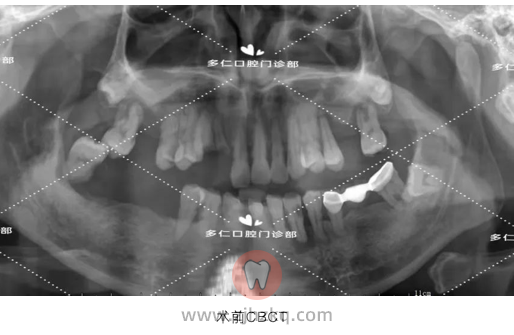

患者自述:下颌多颗牙刷牙出血,咀嚼疼痛,松动2年余,现为恢复咀嚼,来院就诊。

医生建议:35-31、37、42-44、48分离牙龈,拔除, 即拔即种32、34、36、42、44、46植入植体6颗,即刻修复,当天戴牙,后期恢复6-6全瓷牙冠。